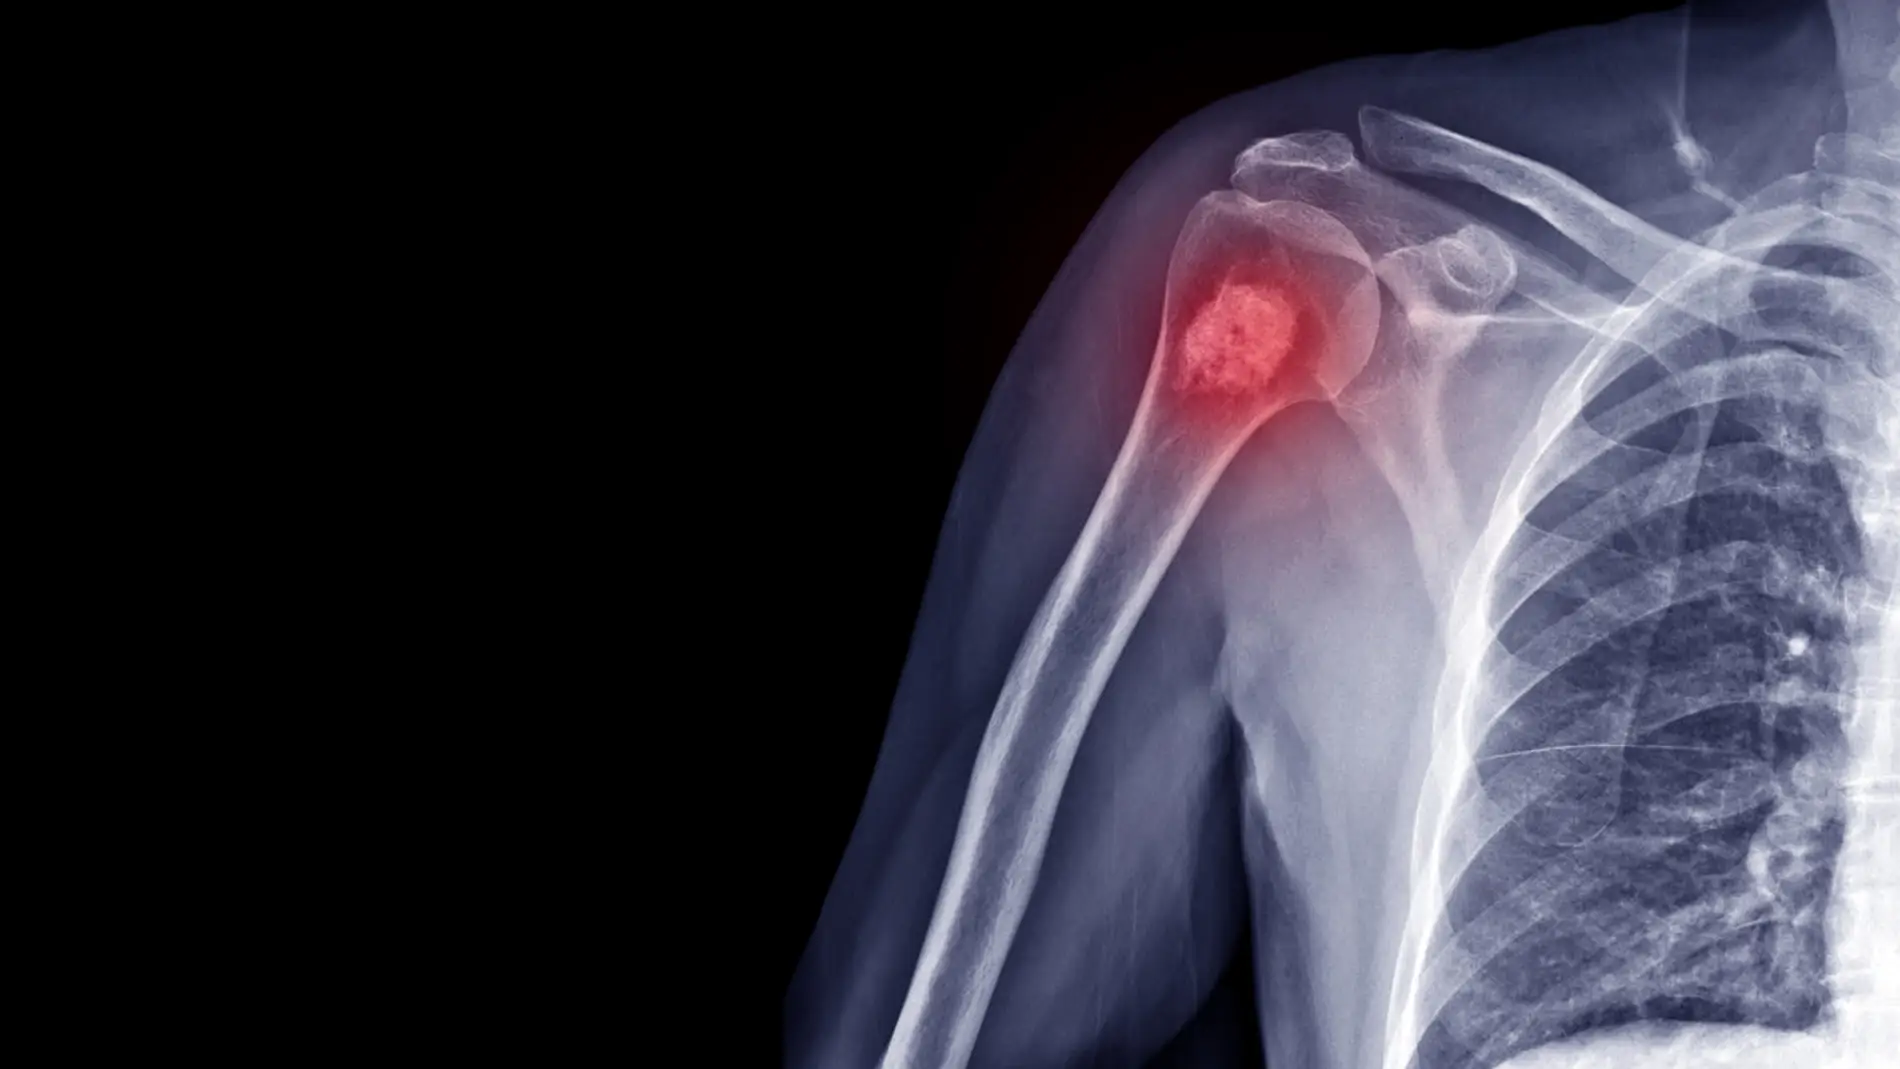

Cáncer de huesos, la verdadera causa de la muerte de la reina Isabel II: síntomas y causas

Es poco habitual que un cáncer comience en el hueso. Lo más normal es que llegue hasta allí a través de una metástasis procedente de otro tumor. Este tipo de cáncer puede aparecer en cualquier hueso, pero suele afectar al fémur.

Existen tres tipos de cáncer de hueso: el osteosarcoma, el condrosarcoma y el sarcoma de Ewing. Tal y como explican en Mayo Clinic, el primero es un tipo de cáncer de hueso que comienza en las células que forman los huesos. Es el tipo más común de cáncer de hueso. Suele aparecer con más frecuencia en adolescentes y jóvenes adultos, pero también puede aparecer en niños y adultos mayores.

El condrosarcoma es un tipo de cáncer que, por lo general, comienza en los huesos, pero a veces puede presentarse en el tejido blando. El condrosarcoma es más frecuente en la pelvis, la cadera y el hombro. Con mayor frecuencia, aparece en adultos de mediana edad y adultos mayores.